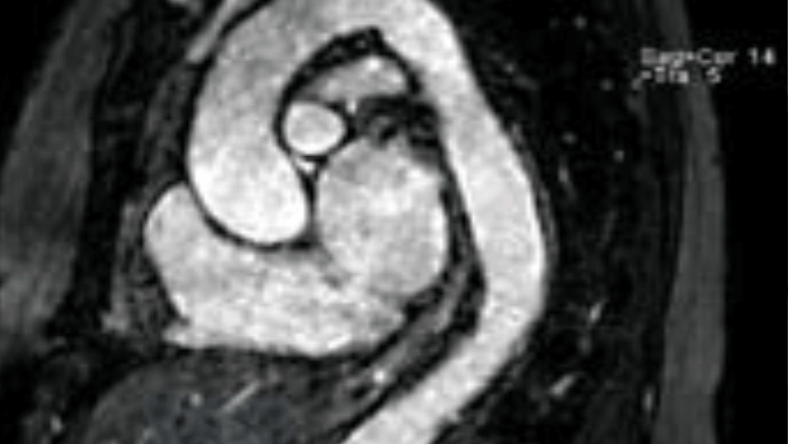

Echocardiography and Cardiac MRI both assess the size and function of the heart muscle and its valves. Cardiac MRI goes one step further however and provides a ‘virtual biopsy’ of the heart, often allowing the cardiologist to determine not only if there is scar of the heart muscle but also what caused the scar in the first place. Cardiac MRI is also the gold standard for precise quantification of heart function. Unlike CT, there is no radiation involved in MRI. International guidelines now place Cardiac MRI as a key investigation in a number of presentations including: heart failure of unknown cause; heart attack without explanation on angiography; assessment of heart muscle ‘viability’ after a heart attack; inherited cardiomyopathies; unexplained masses in the heart; and unexplained thickening of the heart muscle. MRI is also ideal for the surveillance of a dilated aorta, with advanced sequences allowing us to obtain high-resolution imaging with no contrast, no needles, and no radiation. At Western Radiology, our cardiologist has experience in all major indications for Cardiac MRI; please contact us for further details.

Cardiac MRI is a highly sub-specialised imaging modality that requires significant expertise beyond that acquired during standard cardiology or radiology training. Our cardiologist has a specialist interest in Cardiac MRI with years of experience and is one of the very few cardiologists in WA to hold Level III accreditation (highest level) of training with the Society of Cardiovascular MRI. As a testament to the importance we place on quality, each study at Western Radiology is supervised by our cardiologist who can then individualise the study in real-time to ensure the study is of the highest calibre.